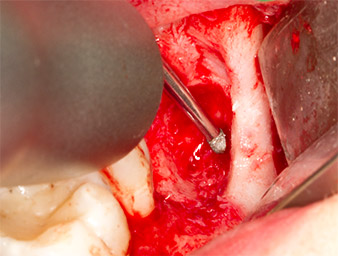

Pour obtenir un matériau autogène en vue du traitement ultérieur de la plaie, des fragments osseux sains sont collectés autour du reste radiculaire à l'aide d’un insert piézochirurgical (Piezomed B5) (Fig. 5).

Le tissu autogène est extrait à l’aide de la section en forme de racloir de la pièce active de l’insert et conservé dans un soluté physiologique isotonique jusqu’à utilisation ultérieure (cf. Fig. 13).

Pour exposer le reste radiculaire en minimisant le traumatisme causé aux tissus, un autre insert est utilisé (Piezomed S2) qui est principalement indiqué pour la préparation de la fenêtre latérale dans les élévations de plancher sinusien. La boule diamantée est également utilisée pour adoucir les bords osseux tranchants (Fig. 6 et 7). Tous les inserts Piezomed sont utilisés avec le paramétrage par défaut automatique, et sans la fonction Booster.